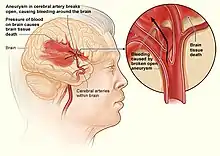

| |

| Internal bleeding in the brain | |

Internal bleeding (also called internal haemorrhage) is a loss of blood from a blood vessel that collects inside the body, and is not usually visible from the outside.[1] It can be a serious medical emergency but the extent of severity depends on bleeding rate and location of the bleeding (e.g. head, torso, extremities). Severe internal bleeding into the chest, abdomen, pelvis, or thighs can cause hemorrhagic shock or death if proper medical treatment is not received quickly.[2] Internal bleeding is a medical emergency and should be treated immediately by medical professionals.[2]

- Blood vessel rupture as a result of high blood pressure, aneurysms, peptic ulcers, or ectopic pregnancy.[8]